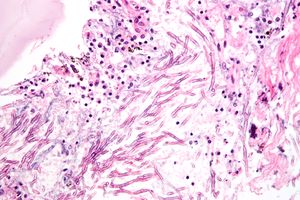

الرشاشيات

Aspergillosis. H&E stain.